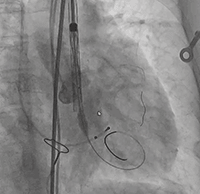

行左冠保护,预置左冠球囊

● 第一次释放,初步张开后给予160次/分起搏,起搏后血压未降低反而升高至约135/80mmHg,释放前1/3过程中发生上跳,故回收。

● 第二次释放,初始定位在瓣下4mm,瓣膜张开后起搏,血压仍不降反升,仍在前1/3释放中发生上跳,故回收。

● 第三次释放,定位瓣下4mm再次尝试,起搏后释放,仍有上跳趋势,故回收。

● 第四次释放,定位约瓣下8mm,瓣膜初始张开后,略提拉寻找锚定位置,至瓣下4mm位置,起搏准备释放至工作位,仍有上跳趋势,故回收,考虑到远期患者获益,更换新瓣膜尝试。

第三折:定位难

● 更换新瓣膜跨瓣后,猪尾难以送至无冠窦底,故行造影定位窦底。

隐约可见“无冠窦”后部更深窦底,位于“无冠窦”下约6mm,参考该位置后进行0位定位,无起搏逐步释放至工作位,瓣膜无明显位移表现,瓣膜形态压缩良好,造影评估无反流。准备释放瓣膜。

无张力释放,脱钩后瓣膜略微下滑,约位移瓣环下4~5mm位置,瓣膜整体形态良好,造影评估无可见反流。

超声评估,微量瓣周反流,二尖瓣工作良好,植入位置理想。

结束手术,一波三折终成功!